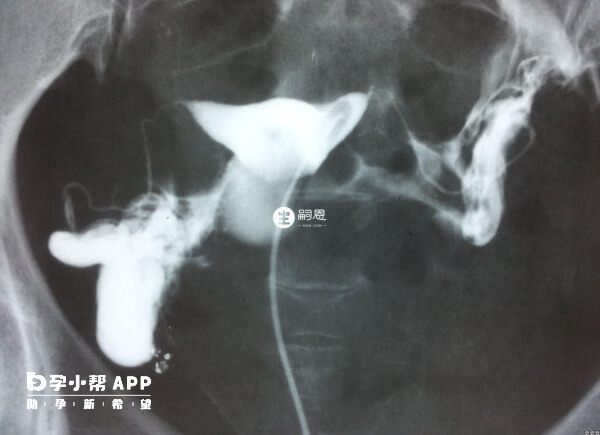

單側輸卵管堵塞有炎症的患者還可考慮腹腔鏡手術改善症狀,比如輸卵管粘連分離術、輸卵管傘端整形術、輸卵管造口術等。

輸卵管一側不同並且伴隨比較嚴重的驗證患者,還可採取宮腔鏡手術治療,此種方式主要是輸卵管插管通液,以達到治療的目的。